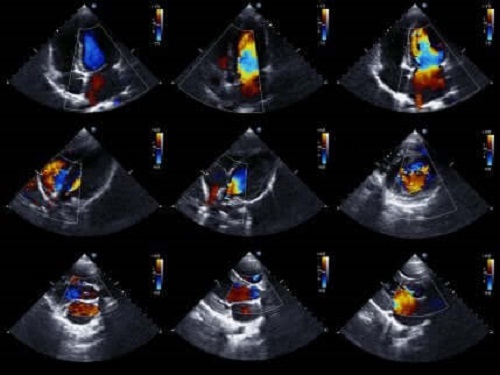

Ekokardiyogram

Son olarak, ekokardiyogramlar, ya da kalp sonogramları, tıbbi profesyonellerin kalbi daha ayrıntılı şekilde incelemesine izin verir.

Ekokardiyogram son derece popüler olan bir tıbbi testtir. Çünkü bu test kalbin hareket eden resimlerini çekebilir. Bundan dolayı, iskemi teşhisini onaylamak veya reddetmek üzere kalbin odacıklarının durumunu ve hareketlerini değerlendirebilir.

Ek olarak, kalbin boyutunu ve gücünü, ve kalp odacıklarının duvarlarının durumunu da değerlendirir. Sonuç olarak, hasta için herhangi bir risk yaratmayan noninvaziv bir testtir. Bunun nedeni kalbin görüntülerini elde etmek için ultrason dalgaları kullanmasıdır.

Eğer doktor bu testi kullanırsa, kalp duvarındaki harekette herhangi bir problem olmaması iskemi olması ihtimalini eleyebilmesini sağlayacaktır. Ne de olsa, akut koroner sendrom kalp duvarı hareketinde problemler görünen tek hastalık değildir. Bundan dolayı, hem test sonuçları hem de semptomlar hesaba katılarak teşhis koyulmalıdır.